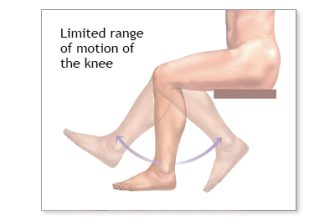

Have you ever experienced difficulty moving a joint